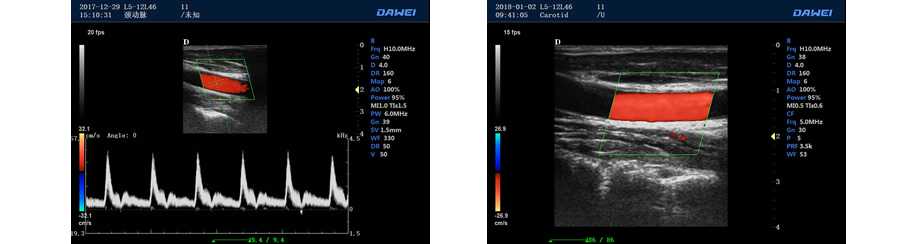

●彩色多普勒血流成像單元

多普勒模式

具有PW脈沖波多普勒和CW連續(xù)波多普勒

取樣容積大小,可視可調(diào)

采樣角度校正:-30-80度

脈沖重復(fù)頻率多段可調(diào)

實(shí)時自動多普勒包絡(luò)描述及自動測量與分析

外周血管 多普勒血流測量與分析